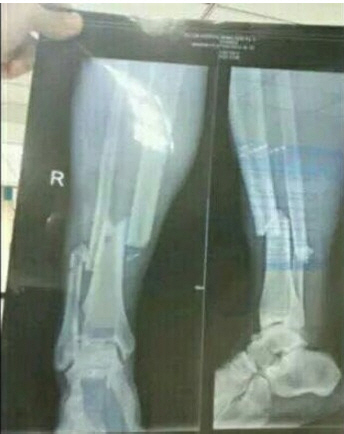

잉글랜드 프리미어리거 출신 공격수 뎀바바(31·상하이 선화)가 왼쪽 다리뼈가 골절되는 중상을 입었다. 선수생명이 기로에 놓였다.

뎀바 바는 뉴캐슬과 첼시에서 활약한 세계적인 공격수 출신으로 EPL에서만 통산 99경기 43골을 기록했다. 터키리그를 거쳐 지난해 7월 무려 1200만 파운드(약 182억원)의 이적료로 상하이 선화에 입단했다. 올 시즌 슈퍼리그 18경기에서 14골을 터뜨리며 리그 득점 1위를 달리는 가운데 불의의 부상 악재가 닥쳤다. 그레고리오 만자노 상하이 선화 감독은 "뎀바 바의 선수생명이 끝날 수도 있다"며 부상이 심상치 않음을 알렸다.